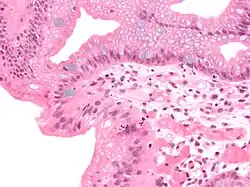

Both macroscopic (from endoscopy) and microscopic positive findings are required to make a diagnosis. Barrett's esophagus is marked by the presence of columnar epithelia in the lower esophagus, replacing the normal squamous cell epithelium—an example of metaplasia. The secretory columnar epithelium may be more able to withstand the erosive action of the gastric secretions; however, this metaplasia confers an increased risk of adenocarcinoma.[17]

Intestinal metaplasia

The presence of goblet cells, called intestinal metaplasia, is necessary to make a diagnosis of Barrett's esophagus. This frequently occurs in the presence of other metaplastic columnar cells, but only the presence of goblet cells is diagnostic. The metaplasia is grossly visible through a gastroscope, but biopsy specimens must be examined under a microscope to determine whether cells are gastric or colonic in nature. Colonic metaplasia is usually identified by finding goblet cells in the epithelium and is necessary for the true diagnosis.[25]

Many histologic mimics of Barrett's esophagus are known (i.e. goblet cells occurring in the transitional epithelium of normal esophageal submucosal gland ducts, "pseudogoblet cells" in which abundant foveolar [gastric] type mucin simulates the acid mucin true goblet cells). Assessment of relationship to submucosal glands and transitional-type epithelium with examination of multiple levels through the tissue may allow the pathologist to reliably distinguish between goblet cells of submucosal gland ducts and true Barrett's esophagus (specialized columnar metaplasia). The histochemical stain Alcian blue pH 2.5 is also frequently used to distinguish true intestinal-type mucins from their histologic mimics. Recently, immunohistochemical analysis with antibodies to CDX-2 (specific for mid and hindgut intestinal derivation) has also been used to identify true intestinal-type metaplastic cells. The protein AGR2 is elevated in Barrett's esophagus[26] and can be used as a biomarker for distinguishing Barrett epithelium from normal esophageal epithelium.[27]

The presence of intestinal metaplasia in Barrett's esophagus represents a marker for the progression of metaplasia towards dysplasia and eventually adenocarcinoma. This factor combined with two different immunohistochemical expression of p53, Her2 and p16 leads to two different genetic pathways that likely progress to dysplasia in Barrett's esophagus.[28] Also intestinal metaplastic cells can be positive for CK 7+/CK20−.[29]

Epithelial dysplasia

After the initial diagnosis of Barrett's esophagus is rendered, affected persons undergo annual surveillance to detect changes that indicate higher risk to progression to cancer: development of epithelial dysplasia (or "intraepithelial neoplasia").[30] Among all metaplastic lesions, around 8% were associated with dysplasia. particularly a recent study demonstrated that dysplastic lesions were located mainly in the posterior wall of the esophagus.[31]

Considerable variability is seen in assessment for dysplasia among pathologists. Recently, gastroenterology and GI pathology societies have recommended that any diagnosis of high-grade dysplasia in Barrett be confirmed by at least two fellowship-trained GI pathologists prior to definitive treatment for patients.[17] For more accuracy and reproducibility, it is also recommended to follow international classification systems, such as the "Vienna classification" of gastrointestinal epithelial neoplasia (2000).[32]